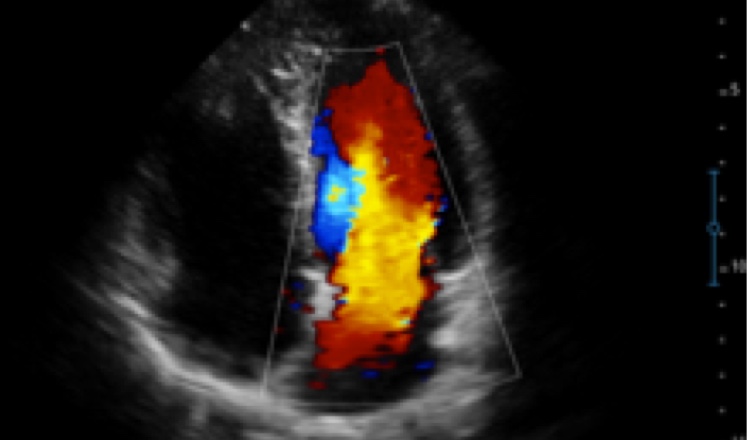

X5便携式彩色多普勒超声诊断系统

X5采用前端的超声专用芯片,将台式机大规模集成电路完美压缩在笔记本超声的精巧下,提高了系统的运算速度,加载μ-Scan微米成像、脉冲反相谐波等技术,带来优异的临床表现,清晰呈现高分辨率二维图像和层次丰富的血流图像

X5具备实时宽景成像、穿刺增强、彩色M型、组织多普勒等多种高级成像功能,全方位满足多个科室的诊断需求,整机系统向智能化跨越